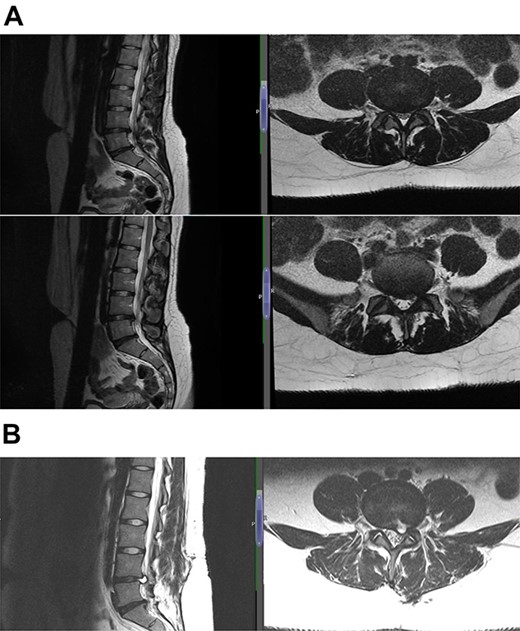

The diagnosis was reached keeping in mind the radiological and contrast scan was taken in follow-up period (Figs 1, 2a, b,3a, b and4a, b). On MRI, it was noted that the cyst was well-defined, smooth regular margins with T1 hypointense and T2 hyperintense and an evident communicating stalk with the disc while in post-gadolinium scan showed cyst wall enhancement. As discography is no longer required for reaching a diagnosis, it was not done in any of the patients.

(A) Case 3—an early MRI demonstrates at L5/S1 level moderate diffuse disc bulge is seen with early bilateral facet joint degenerative changes; there is irritation of the L5 nerve roots bilaterally, and at L5/S1 level moderate left posterolateral disc bulge is seen irritating the S1 nerve roots bilaterally left more than right, and bilateral facet joint degenerative changes also noted at this level, and (B) case 3—a later MRI, the cystic changes noted at the L4-L5 level which clearly shows a connection with the intervertebral disc.